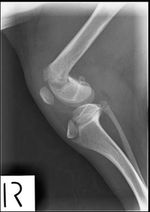

I discovered that in mid-2009, Boo Boo had both of his hind legs broken when he                     was about 5-6 months old. I located the clinic where the surgery was carried out.                     After dropping him off there, Boo Boo’s “caregivers” disappeared for 2 months. Finally                     the clinic tracked them down and they came in to collect him. They paid a fraction                     of the bill and instructed that there was no need for further X-rays. The vet told                     me he was very concerned that Boo Boo had not been back to the clinic for a post                     operative check up, because his bones were still growing and the pins may be causing                     him pain.

I have now had Boo Boo vet checked, X-rayed, neutered, nails clipped, vaccinated, micro-chipped, registered, flea and worm treated and had his teeth de-scaled and polished, etc. The vet found a very painful area on his right leg where he could feel one of the cross pins protruding at a strange angle. The left leg, which Boo Boo lifts in discomfort, will also need to be opened up and will probably also have the pins removed.